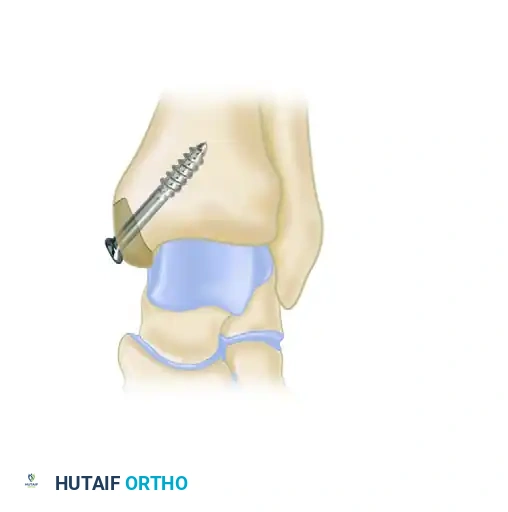

Diagram illustrating access to the talar dome, highlighting the necessity of medial malleolar osteotomy for deep posterior-medial lesions.

When large, posterior-medial lesions require structural grafting (OATS) or direct fixation, an open approach via medial malleolar osteotomy is required.

- Incision: A longitudinal incision is made over the medial malleolus.

- Pre-drilling: Before the osteotomy, two parallel holes are drilled from the tip of the medial malleolus proximally into the tibial metaphysis. These are tapped for 4.0-mm cancellous screws to ensure perfect anatomic reduction during closure.

- Osteotomy: A chevron-type (V-shaped) osteotomy is performed using an oscillating saw, directed toward the axilla of the medial clear space. The osteotomy is completed with an osteotome to preserve bone dust and create a rough surface for healing.

- Exposure: The medial malleolus is reflected inferiorly on its intact deltoid ligament hinge, exposing the medial talar dome.